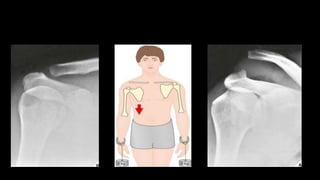

O documento aborda lesões no ombro, dividindo-as por faixas etárias: fraturas de clavícula em crianças, luxações em adultos e fraturas do úmero proximal em idosos. Descreve também técnicas de avaliação radiográfica e suas variações, incluindo incidências específicas para diagnóstico. Além disso, são mencionados métodos de imagem alternativos para a avaliação de partes moles e condições articulares.